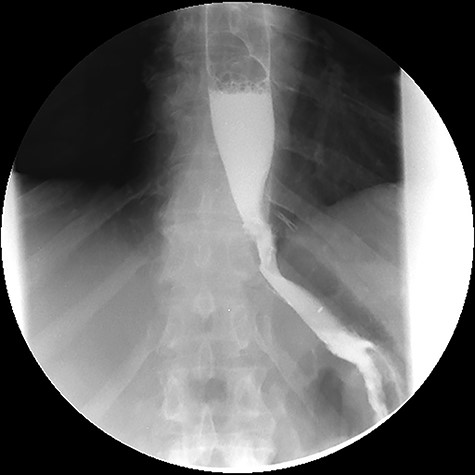

At the 24-month follow-up, an upper endoscopy confirmed integrity of the stomach pouch and GJA without any GGF (see Fig. 10). Thirty-six months after surgical treatment of the GGF, the patient remains asymptomatic and has a stable BMI.

Esophagogastroduodenoscopy image showing a normal gastric pouch with only one orifice corresponding to the gastro-jejunal anastomosis (arrow).